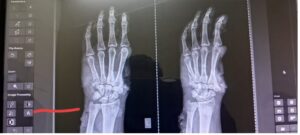

बिलासपुर,,, कानन पेंडारी जू में आज एक गंभीर घटना घटित हुई! जब विभागीय अधिकारी के लापरवाही के चलते एक बाघिन ने कर्मचारी पर हमला कर दिया! बघिन ने कर्मचारी का अंगूठा काट लिया! और बाएं हाथ की एक उंगली फ्रेक्चर हो गई! घटना के बाद कर्मचारी को तुरंत सिम्स मेडिकल कॉलेज में भर्ती कराया गया! स्थिति नाजुक बताई जा रही है! और डॉक्टरों ने उसे बेहतर इलाज के लिए बाहर भेजने की सलाह दी! लेकिन डीएफओ गणेश यूआर ने उसे बाहर इलाज के लिए भेजने से मना कर दिया!